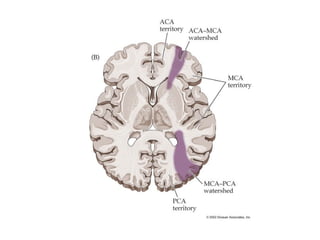

Vascular territories of the brain

Watershed zones